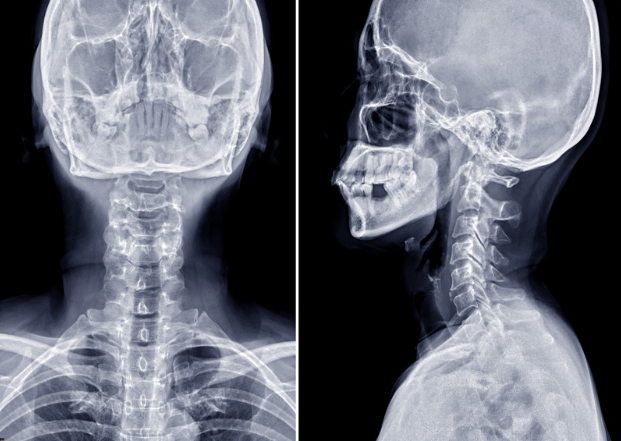

まずレントゲンを撮像し、正面と側面、顎を引いた状態、顎を上げた状態での頸椎の骨の並びや動揺があるかを評価し診断を行います。

首の痛みが悪化しない範囲で撮影しますので、ご安心ください。